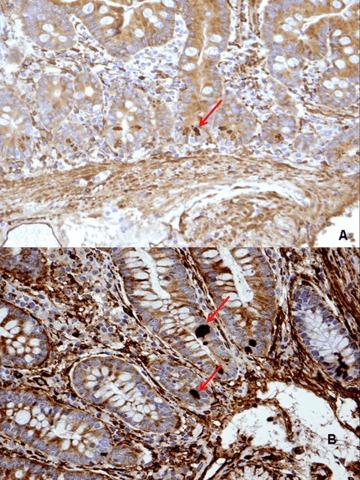

Tissue transglutaminase (tTG) plays an important role in celiac disease pathogenesis and antibodies to tTG are a diagnostic marker of gluten-sensitive enteropathy. The aim of this study was to investigate the localization of tTG in the duodenal mucosa in control tissues and in different histological stages of celiac disease by using a commercial and a novel set of anti-tTG monoclonal antibodies, to see whether this assessment can be useful for diagnostic purpose. The distribution of tTG was firstly evaluated in 18 untreated celiac patients by using a commercial monoclonal antibody (CUB7402) against tissue transglutaminase enzyme and directed against the loop-core region of the enzyme. Thereafter, in further 30 untreated celiac patients we employed three newly characterized anti-tTG monoclonal antibodies produced against recombinant human-tTG. The epitopes recognized are located in three distinct domains of the protein corresponding to the core, C1 and C2 protein structure. Eleven age- and sex-matched patients with chronic duodenitis acted as controls. All subjects underwent upper endoscopy to obtain biopsy samples from the duodenum. Overall, we found that (i) tTG is equally expressed in CD at different stages of disease; (ii) tTG is expressed, at similar level, in CD and controls with duodenitis. Assessment of tTG level in biopsy samples by immunohistochemical methods is not useful in the clinical diagnostic work-up of CD.

组织转谷氨酰胺酶(tTG)在乳糜泻发病机制中起重要作用,抗tTG抗体是麸质敏感性肠病的诊断标志物。本研究的目的是通过使用一种商用和一组新型抗tTG单克隆抗体,研究tTG在对照组织以及乳糜泻不同组织学阶段十二指肠黏膜中的定位,以观察这种评估是否对诊断有帮助。首先,使用一种针对组织转谷氨酰胺酶且靶向该酶环-核心区域的商用单克隆抗体(CUB7402),对18例未经治疗的乳糜泻患者的tTG分布进行评估。此后,在另外30例未经治疗的乳糜泻患者中,我们使用了三种新鉴定的针对重组人tTG产生的抗tTG单克隆抗体。所识别的表位位于蛋白质对应于核心、C1和C2蛋白质结构的三个不同结构域中。11例年龄和性别匹配的慢性十二指肠炎症患者作为对照。所有受试者均接受上消化道内镜检查以获取十二指肠活检样本。总体而言,我们发现:(i)tTG在疾病不同阶段的乳糜泻中表达水平相当;(ii)tTG在乳糜泻患者和十二指肠炎症对照患者中的表达水平相似。通过免疫组织化学方法评估活检样本中的tTG水平对乳糜泻的临床诊断检查并无帮助。